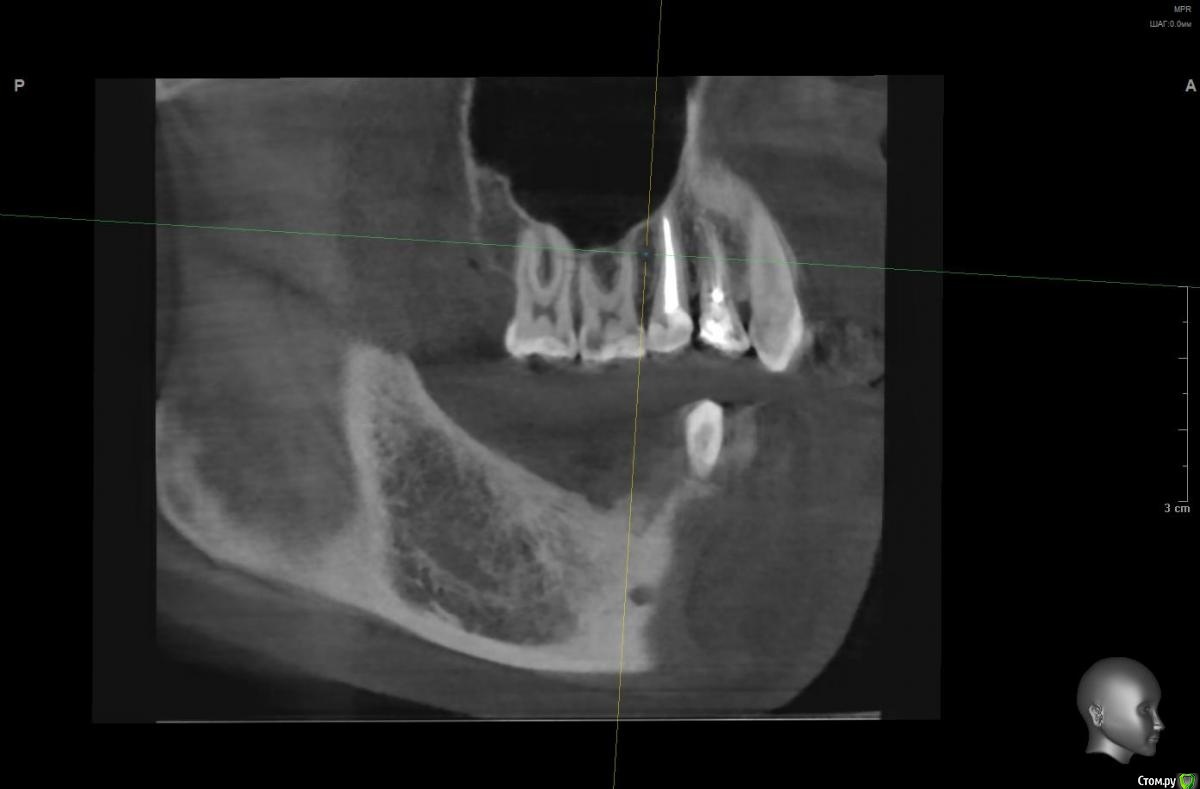

Vords Опубликовано 20 ноября, 2020 Поделиться Опубликовано 20 ноября, 2020 Доброго дня, форумчане. Прошу прощения за беспокойство. Хотел бы попытать счастье на форуме, поскольку все проведенные до этого консультации результатов не дали (( В общем ситуация такая: В начале сентября была неудачная попытка имплантации 46 и 47 зубов. 46 был удален и поставлены импланты nobel сразу в 46 и 47. В результате образовалась большая гематома и 2 недели были достаточно сильные боли в результате которых импланты были извлечены. После этого боль стала значительно более терпима и с ней я живу до сегодняшнего дня. И вроде уже через 20 дней нужно идти на вторую попытку имплантации, но боль еще не прошла. Никто (несколько терапевтов, имплантологов на КТ не видят причин для такой боли) - и идей ни у кого нет (( Было предположение, что отдает 45, так как очень сильно оголились корни после удаления 46 и его депульпировали, но боль не прошла. На данный момент идей совсем не осталось (кроме мифической идеи, что, возможно, 6 зуб сверху имеет пульпит (по теням на КТ) и отдает вниз. Я буду очень благодарен если у кого-то будут хоть какие-то идеи по этому вопросу, потому что жить с этой постоянной (пусть и не сильной) болью становится невозможно. Готов идти на очные консультации (но и было уже настолько много, что я, если честно, не уверен в их смысле). Ссылка на КТ https://yadi.sk/d/S3hKfHUWO-UTQg Сейчас пытаюсь разобраться как сделать качественные скрины нужных мест.Пока не выходит =(( Заранее благодарю. Ссылка на комментарий

wladdX Опубликовано 20 ноября, 2020 Поделиться Опубликовано 20 ноября, 2020 На н/челюсти ничего необычногоА вот вероятность пульпита зуба 16 довольно высокая 1 Ссылка на комментарий

Vords Опубликовано 20 ноября, 2020 Автор Поделиться Опубликовано 20 ноября, 2020 (изменено) На н/челюсти ничего необычногон_ч.jpgА вот вероятность пульпита зуба 16 довольно высокая16_1.jpg16_2.jpgБлагодарю, что нашли время ответить. А по Вашему опыту может ли так отдаваться вниз от 16? Или это "натянутая" версия? 16 не беспокоит от слова совсем Изменено 20 ноября, 2020 пользователем Vords Ссылка на комментарий